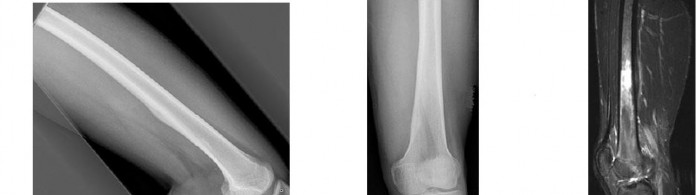

A 15-year-old male presents with deep knee pain awakening him at night. Radiographs show a permeative destructive lesion in the distal femoral metaphysis with a 'sunburst' periosteal reaction and Codman's triangle.

Biopsy confirms high-grade conventional osteosarcoma. What is the most critical prognostic factor for long-term overall survival in this patient?

Explanation

For localized high-grade osteosarcoma, the most important prognostic indicator is the histologic response to neoadjuvant chemotherapy. This is evaluated during the definitive resection. A 'good response' is typically defined as greater than 90% or 99% tumor necrosis. Patients who achieve this level of necrosis have a significantly improved disease-free and overall survival rate compared to 'poor responders' who have extensive viable tumor cells remaining.